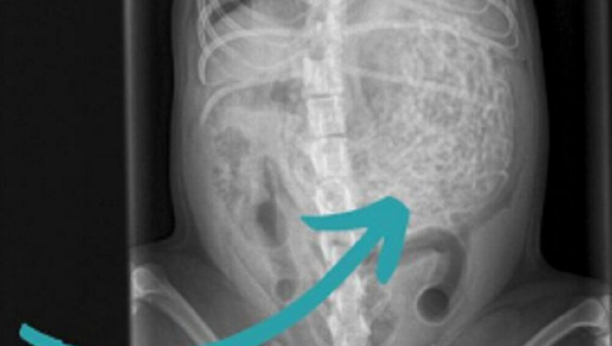

Britanska porodica doživela je pravi šok kada su psa odveli kod veterinara zbog "lošeg osećaja" koji su imali, jer je odjednom postao tih. Tamo je na ultrazvuku otkriveno da je pas pojeo 200 grama gumica za kosu!

Pregled u veterinarskoj ordinaciji pokazao je da pas ima nešto neobično u stomaku, pa su se odmah odlučili na operaciju. Izvađeno mu je oko 60 gumica teških 200 grama, a pas Hem je težak samo šest kilograma.